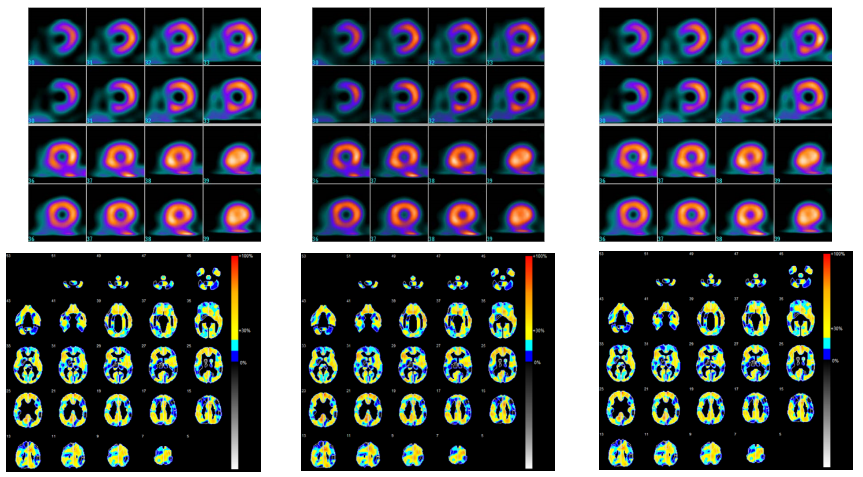

Poniżej zestawiono oceniane obrazy dla porównania.

Rys. 12 Przykładowe obrazy RI (Hybrid Gamma PXL, po lewej, GSDF w środku, 2.2 po prawej)